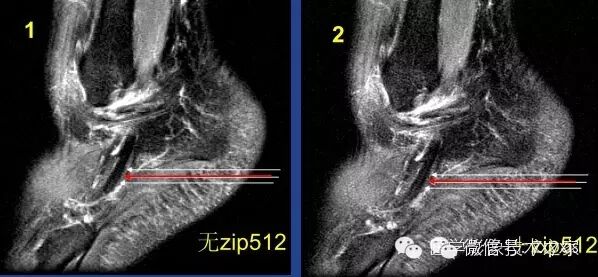

Zip512可以使伪影更佳明显。